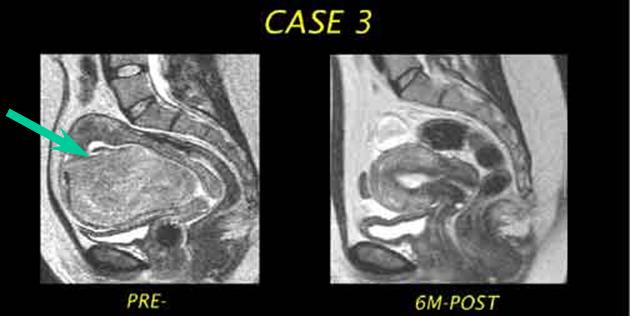

MRI of the Uterus Pre-Embolization and Post-Embolization

| Serial image obtained prior to UFE and 6 months after UFE demonstrates nearly complete elimination of the fibroid. |